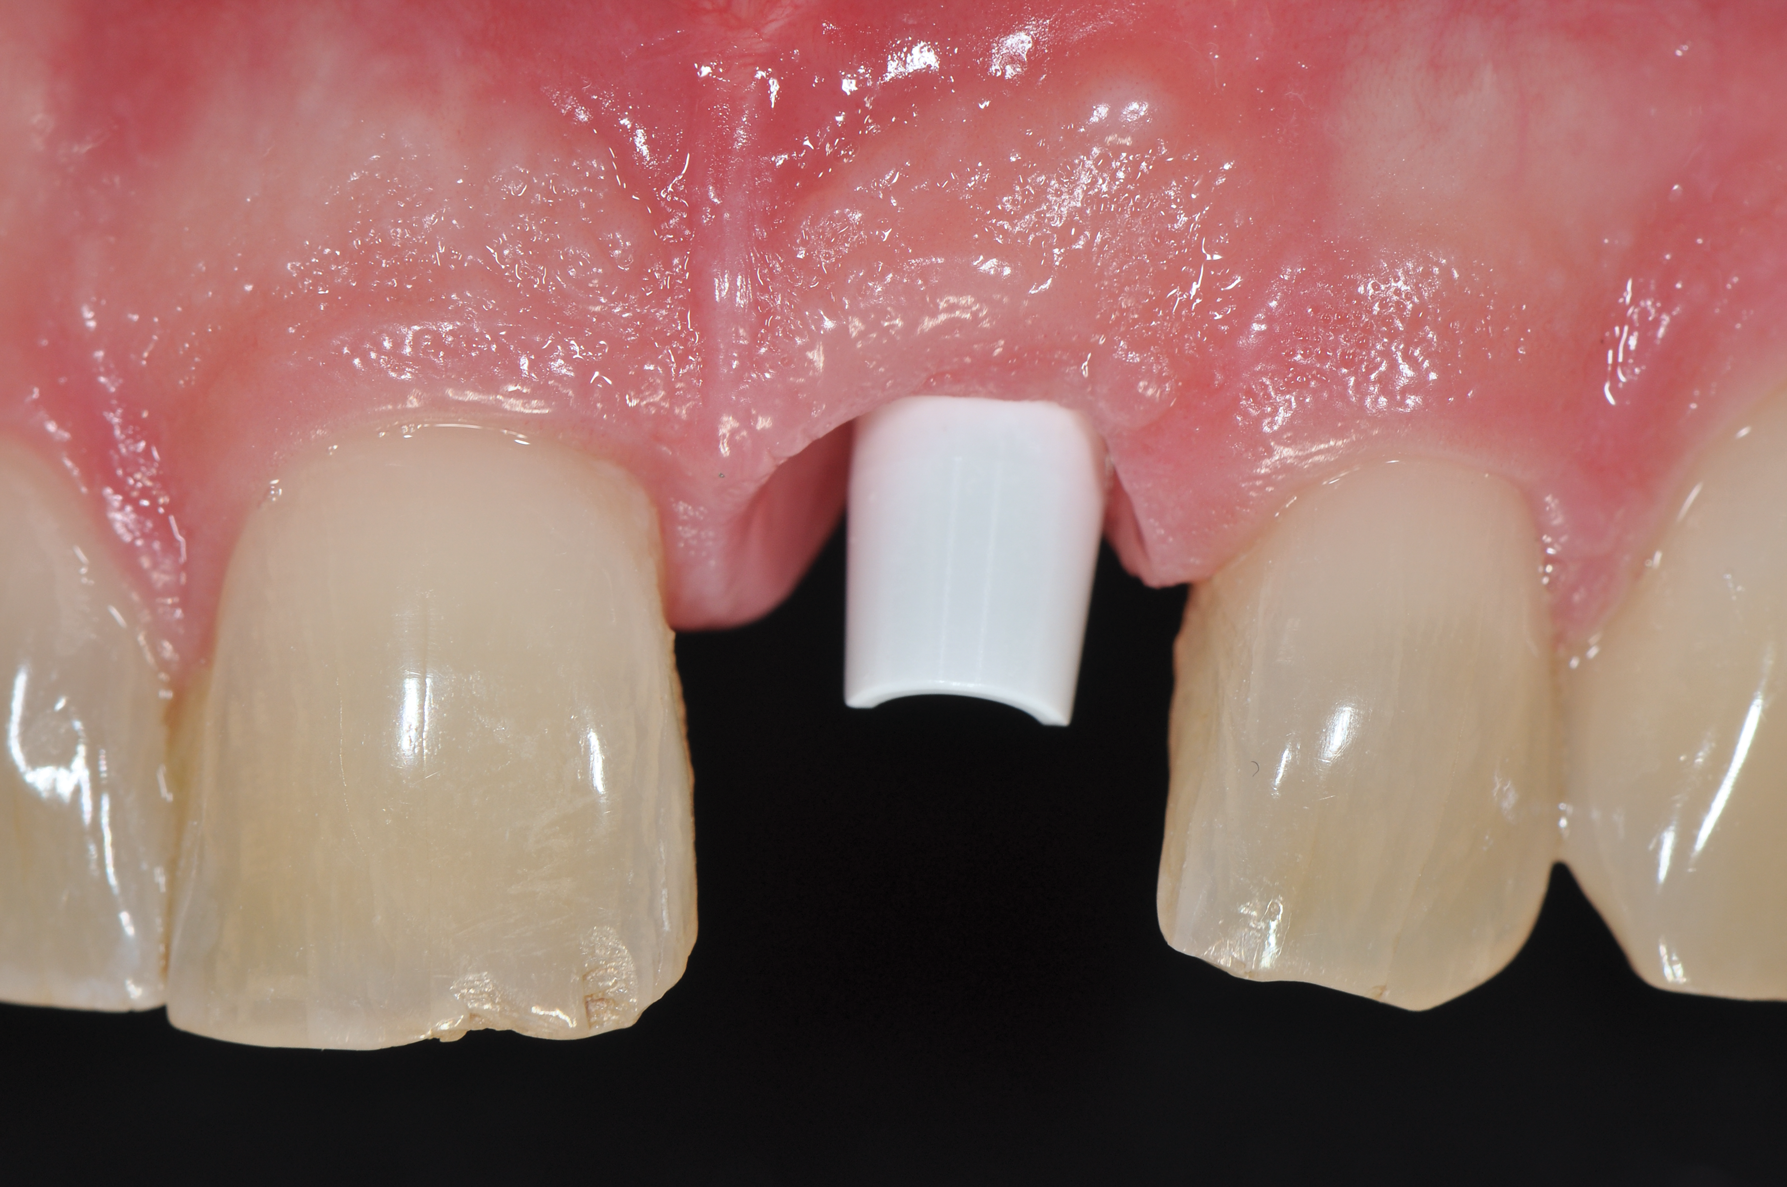

While more scientific evidence showing a lower tendency toward peri-implantitis may still need to be provided for ceramic implants, the essential argument for these implants based on clinical experience is the excellent and almost consistently inflammation-free peri-implant soft-tissue condition (Figure 3).

Fig 3. Soft tissue with zirconia implant free of inflammation.

Figure 3